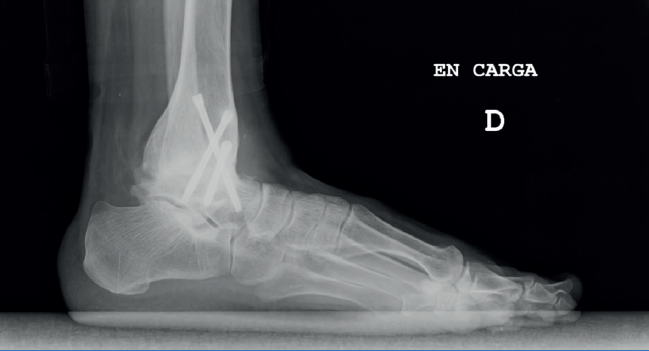

Nuestra experiencia (Figura 1)

Bajo nuestra experiencia, en pacientes intervenidos de artrodesis de tobillo sí que observamos una degeneración progresiva de la articulación en un tercio de los pacientes, pero clínicamente es silente en la mayoría de los pacientes. Asimismo, el número de reintervenciones por dolor es mínimo y se observa un alto grado de satisfacción subjetiva de los pacientes.

Figura 1. Mujer de 42 años con artritis reumatoide. Radiografía del tobillo tras 10 años de artrodesis tibiotalar. Sigue asintomática clínica y radiológicamente.